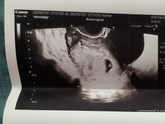

Сходила на узи и грустно теперь. Переживаю, хоть и понимаю, что рано себя накручиваю. ПЯ выросло до 28мм, эмбриончик виден — 5мм, желточный мешочек тоже 5мм. Но сердцебиение не увидели. Узист сказала, что просто рано и совсем маленький. Может узист косячная конечно ? я к ней записалась, т.к. удобно было перед ЖК в эту клинику прийти — рядом они. Она мне сначала вообще нашла кисту в левом яичнике, хотя левый яичник у меня пустой, в нем только мелкие фолликулы. Потом все таки поняла, что киста в правом яичнике. В общем наковыряла мне что-то, я домой приехала, а у меня светло-коричневые выделения. Может из-за полипа конечно. Но я вся в переживаниях. Сердечка нет, выделения эти дебильные. Отслойки или гематомы она не нашла. Ну их и не было так то. Что думать не знаю. 11 июля у меня запись на узи в ЖК. Туда попробую попасть тогда и там посмотреть. Надеюсь все хорошо будет… Еще на 9 число записана к своему узисту. Пока не знаю, пойду или нет. Настроения нет, ничего не хочу сейчас решать. Просто валяюсь и читаю хорошие истории. Сейчас меня нервируют вот какие факты:

1. Нет сердцебиения при ктр 5мм

2. ПЯ 28мм и соответствует 8 неделям. А КТР 5мм и соответствует 6 нед. У меня по месячным 7нед 3 дня, по овуляции 6 нед 3 дн. Короче бесит что они друг другу не соответствуют

3. Желточный мешочек 5мм, это много, обычно на таком сроке он 3-4мм, не больше.

Да, но там ничего не понятно вообще. Просто пятна

Ну у меня вот так. Ничего не понятно?